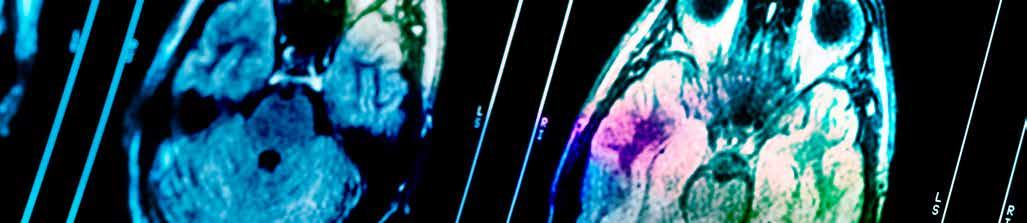

We are proud to offer a comprehensive range of Medicare eligible MRI services using the latest 3T technology & AI for faster, more accurate imaging with improved patient comfort. Our team has over 100 cumulative years of experience in MR reporting.

o Full Medicare eligibility1st and only clinic in Noosa

o Industry leading specialists

o Faster scan times

o Latest 3T technology & AI

NOOSA Radiology has announced the installation of a state-of-the-art Siemens MAGNETOM Lumina 3T MRI scanner, offering full Medicare rebates for eligible patients.

This major upgrade gives Sunshine Coast residents access to world-class imaging technology with little to no outof-pocket expenses. The enhanced MRI licence expands Medicare-funded scan availability, easing financial pressure while improving diagnostic access.

“This is a significant benefit for the local community,” said Dr Drew McMenamin, owner and managing radiologist at Noosa Radiology.

“We’re proud to offer world-class imaging technology with full Medicare access. This allows GPs and specialists greater access to fast, accurate and reliable diagnostics without the financial barrier.”

The Siemens 3T MRI delivers exceptionally fast and detailed images across all areas of the body—especially in neurology, musculoskeletal, breast, abdominal and prostate imaging— thanks to its cutting-edge AI-enhanced

technology and wide-bore patientfriendly design.

Importantly, the new MRI service complements Noosa Radiology’s existing PET/CT capabilities, enabling a full suite of advanced imaging under one roof.

This combination of high-resolution MRI and molecular imaging strengthens the centre’s ability to support early detection, diagnosis, and management of complex conditions, including cancer

and neurological disorders. Noosa Radiology continues to lead the way in independent, locally owned radiology services. The new MRI installation supports its mission to combine advanced technology with personalised care, ensuring patients receive the very best in diagnostic support. For appointments or more information, visit www.noosaradiology.com.au or call (07) 5440 9700.